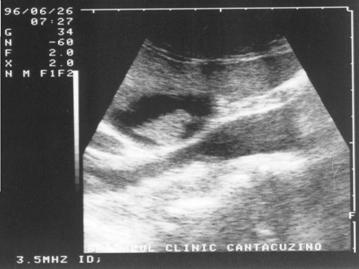

Figura 1. Vezica urinara

Figura 2. Chist renal stang situat in treimea medie

Figura 3. Chist ovar drept

Figura 4. Chist hepatic